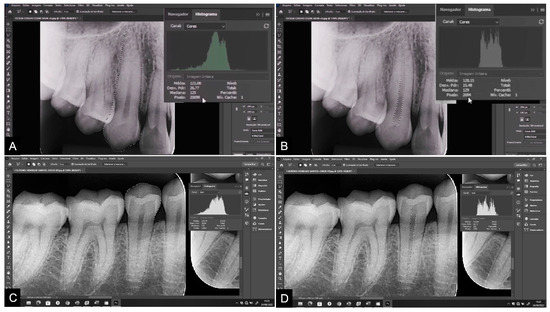

| Measure 1 | Measure 2 | p * | ICC (CI 95%) | |

|---|---|---|---|---|

| Pan T13/23 | ||||

| Tooth area | 19,013 | 18,762 | 0.579 | 0.999 |

| Pulp area | 2110 | 2081 | 0.606 | 0.997 |

| Peri T13/23 | ||||

| Tooth area | 22,501 | 22,686 | 0.643 | 0.990 |

| Pulp area | 2523 | 2552 | 0.239 | 0.996 |

| Pan T35/45 | ||||

| Tooth area | 15,139 | 15,610 | 0.717 | 0.999 |

| Pulp area | 1623 | 1619 | 0.116 | 0.998 |

| Peri T35/45 | ||||

| Tooth area | 15,656 | 15,540 | 0.055 | 0.999 |

| Pulp area | 1534 | 1449 | 0.557 | 0.995 |